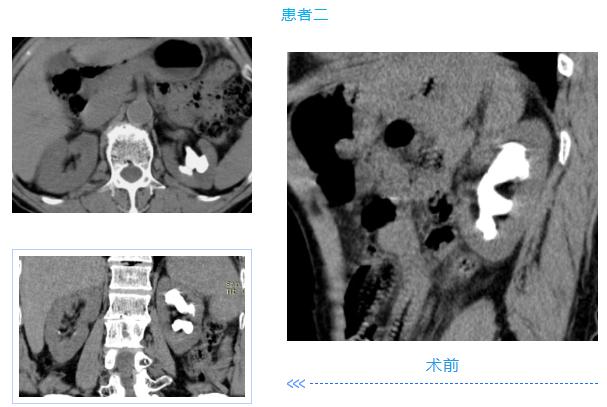

两名患者均为中年男性,入院检查发现肾内多发铸型结石,结石体积大、分布广,其中一例既往患肾行开放取石及经皮肾取石手术,盏颈狭窄伴有肾积水;另一例无明显积水,净石难度高。传统开放手术创伤大、恢复慢,单一微创技术难以彻底清除结石。针对患者病情,泌尿外科团队高度重视,多次组织病例讨论,结合患者身体状况与手术耐受度,最终制定“经皮肾镜+输尿管软镜”联合微创治疗方案。

在泌尿外科团队及麻醉科团队成员密切配合。患者取斜仰截石位,先通过输尿管软镜探查输尿管及肾盂肾盏情况,精准定位结石;随后在超声引导下建立经皮肾通道,置入经皮肾镜,利用钬激光碎石设备将复杂结石击碎成细小颗粒,部分结石因角度问题经皮肾镜无法够到,则通过软镜配合取石篮将结石拖入经皮肾通道口进行彻底清除。整个手术过程创伤小、出血少,术后患者恢复顺利,未出现相关并发症,现已康复出院。